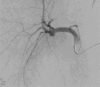

The pseudoaneurysms of the cystic artery (CAP) are very uncommon. They usually develop as a result of an acute cholecystitis or after a cholecystectomy. Among the complications, we can find hemorrhaging, biliary blockage, and haemobilia. Limited understanding of the illness makes managing specific cases difficult. We describe a case of a cystic artery pseudoaneurysm complicating an acute cholecystitis that was successfully treated by transcatheter arterial embolization.